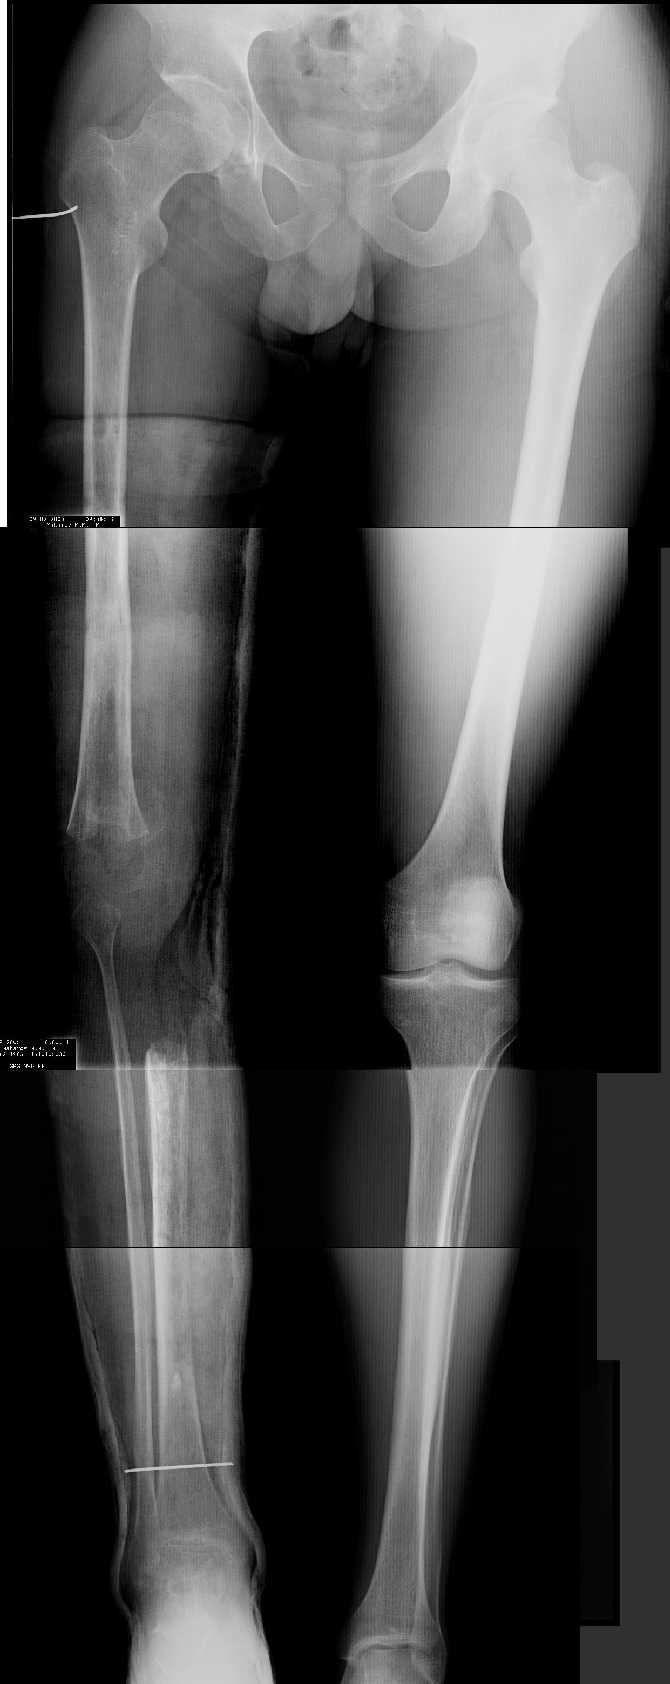

Прежде всего необходимо выполнить рентгенографию в таком положении, как это показано на рис.

После этого представится возможность оценить ось и сравнитьеё с нормой Рисунки из кники Dror Paley - Принципы коррекции деформаций. Этой теме посвящены 800 страниц. Хотя, учитывая контрактуру, это исследование не будет исчерпывающим.

AV> многооскольчатый перелом правой бедреннойљ кости на границе

AV> средней и нижней трети со смещением,

AV> В настоящее время стойкая разгибательная контрактура правого

AV> коленного сустава (сгибание 105-110 гр., разгибание 160-165 гр.),

AV> варусная деформация, болевой синдром.

имеется S-образная деформация бедра на фоне "многооскольчатого

перелома правой бедреннойљ кости на границе средней и нижней трети со смещением"

(хотя "длинные" снимки конечно же не помешали бы...)

На представленных снимках эта деформация как раз и не представлена.

1. Иллюстрации - во вложении.

Два бедра после эндопротезирования.

Авторы операции долго думали почему больная хромает.

Сдклали снимок - одна нога короче почти на 3 см.

Здоровый человек и то будет хромать.

2. Другой пример - дефект после инфицирования коленного эндопротеза.

Предполагалось, что величина дефекта 11-12 см. Так получается, если

сделать снимок только области коленных суставов. Определить

укорочение сложно, так как нога просто болтатется.

Сделали снимок "от и до" - величина дефекта 17 см.

Правда эта иллюстарция сделана на цифровом рентгеновском аппарате.

Больной стоит, а трубка передвигается сверху вних, последовательно

выполняя рентгенограммы. В данном случае - 4 штуки.